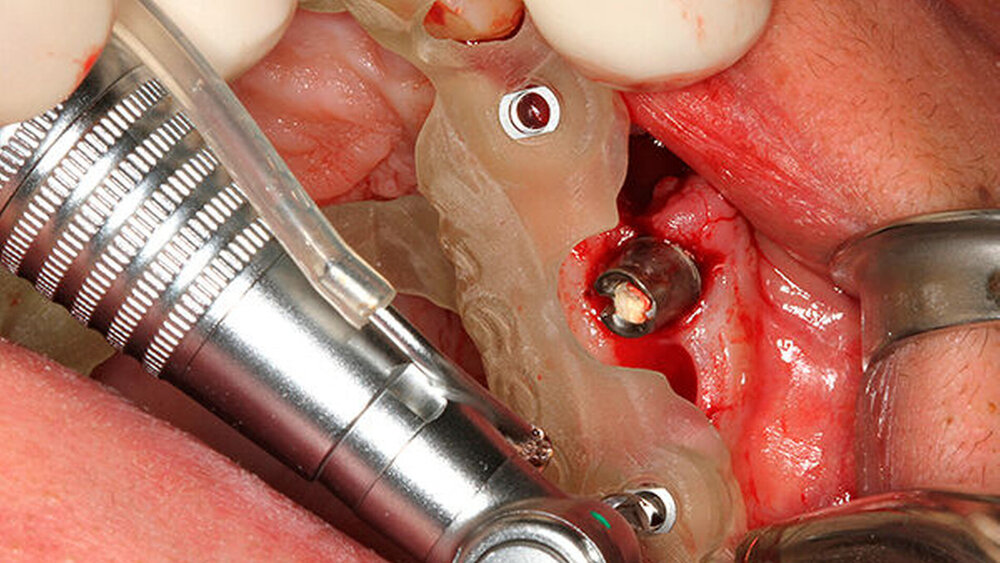

Schnutenhaus:

Ich setze in meiner Praxis 90 Prozent aller Implantate schablonengeführt. Im ästhetischen Bereich halte ich das auch für zwingend notwendig, gerade bei der Sofortimplantationen. Denn nach der Extraktion hilft mir das enorm, die erste Bohrung zu setzen, und verhindert ein Abrutschen im alten Alveolenfach.

Aus meiner Sicht schon. Man muss durch die Kortikalis bohren, dann leicht nach palatinal gehen und dort die richtige Stelle stabil finden. Da hilft die schablonengeführte Implantation sehr.

Noch nicht, aber es wird kommen. Wir behelfen uns mit der CoDiagnostiX-Software, stellen also eine Schablone her, um die Pilotbohrung geführt managen zu können. Es könnte aber noch besser funktionieren, denn wir würden gerne bis zum Schluss voll schablonengeführt vorgehen.